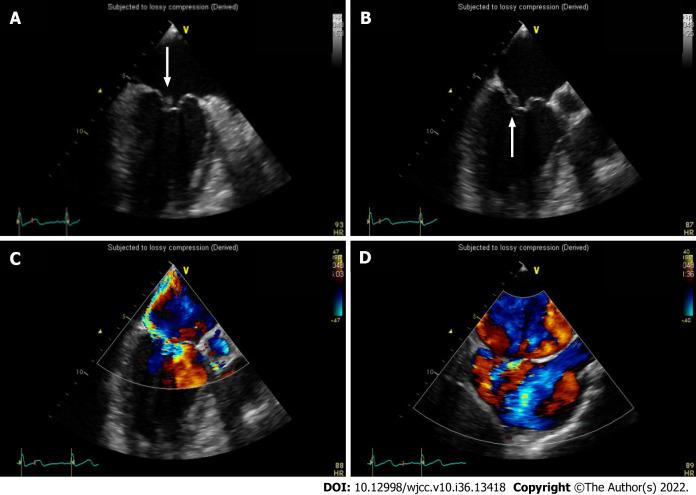

We describe a case of SAB and infective endocarditis in a 43-year-old male who presented with fever of unknown origin and skin diseases. After genetic tests, the skin disease was diagnosed as EHK.

A breached skin barrier secondary to EHK, coupled with inadequate sanitation, likely provided the opportunity for bacterial seeding, leading to IE and deep-seated abscess or organ abscess. EHK may be associated with skin infection and multiple risk factors for extracutaneous infections. Patients with EHK should be treated early to minimize their consequences. If patients with EHK present with prolonged fever of unknown origin, IE and organ abscesses should be ruled out, including metastatic spreads.